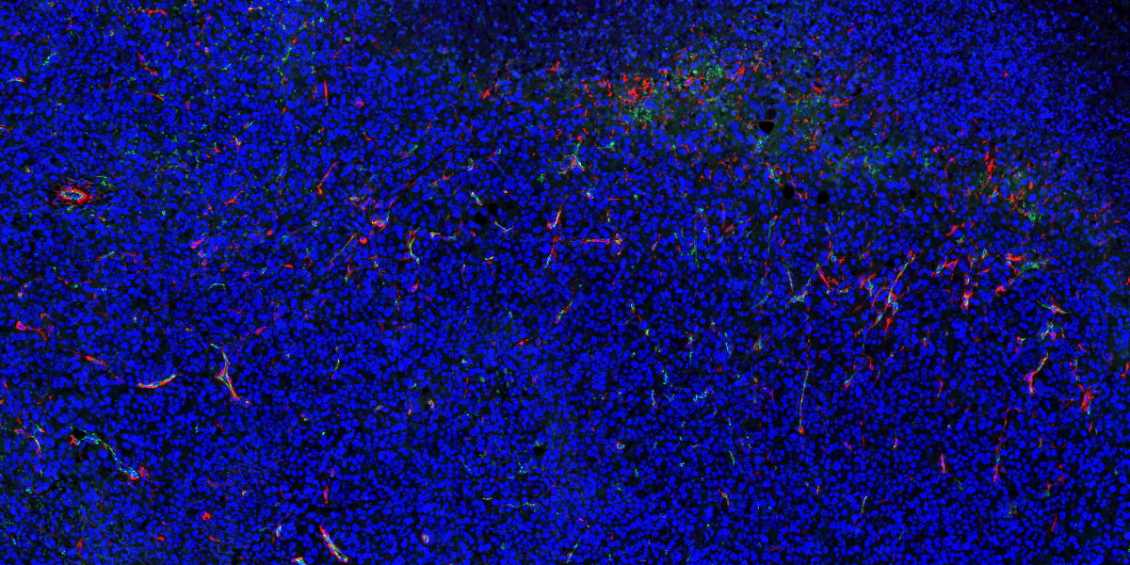

吉林石蜡切片免疫荧光不可避免会产生自发荧光。

4.如若自发荧光很强,严重影响染色效果,亦可采用自发荧光去除剂进行去除。